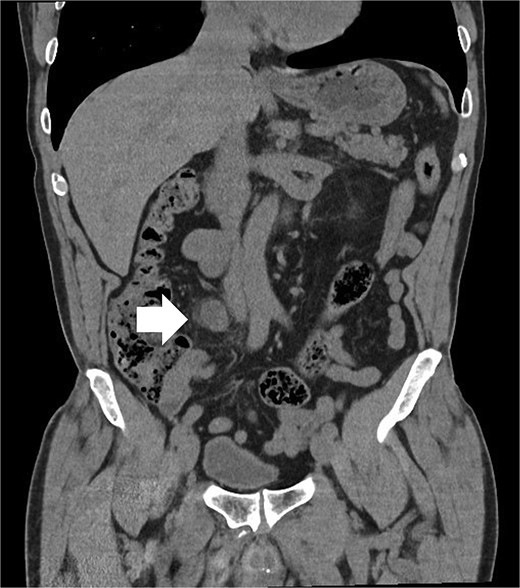

A 64-year-old man with a history of type 2 diabetes, dyslipidemia, and benign prostatic hyperplasia presented to the emergency department following a bicycle accident, resulting in left lumbar trauma. During the patient’s evaluation, an abdominal-perineal computed tomography (CT AP) was requested, which revealed: “Left perirenal hematoma without evidence of active extravasation. A 20x27x24mm nodule (T X AP X CC) in the right para-caval region, approximately at the level of the convergence of the common iliac veins, with heterogeneous and progressive enhancement, possibly indicating a paraganglioma/Zuckerkandl organ.” (Figs 1 and 2). The patient was admitted to the Urology department for conservative treatment, with good clinical evolution, and discharged after 5 days.